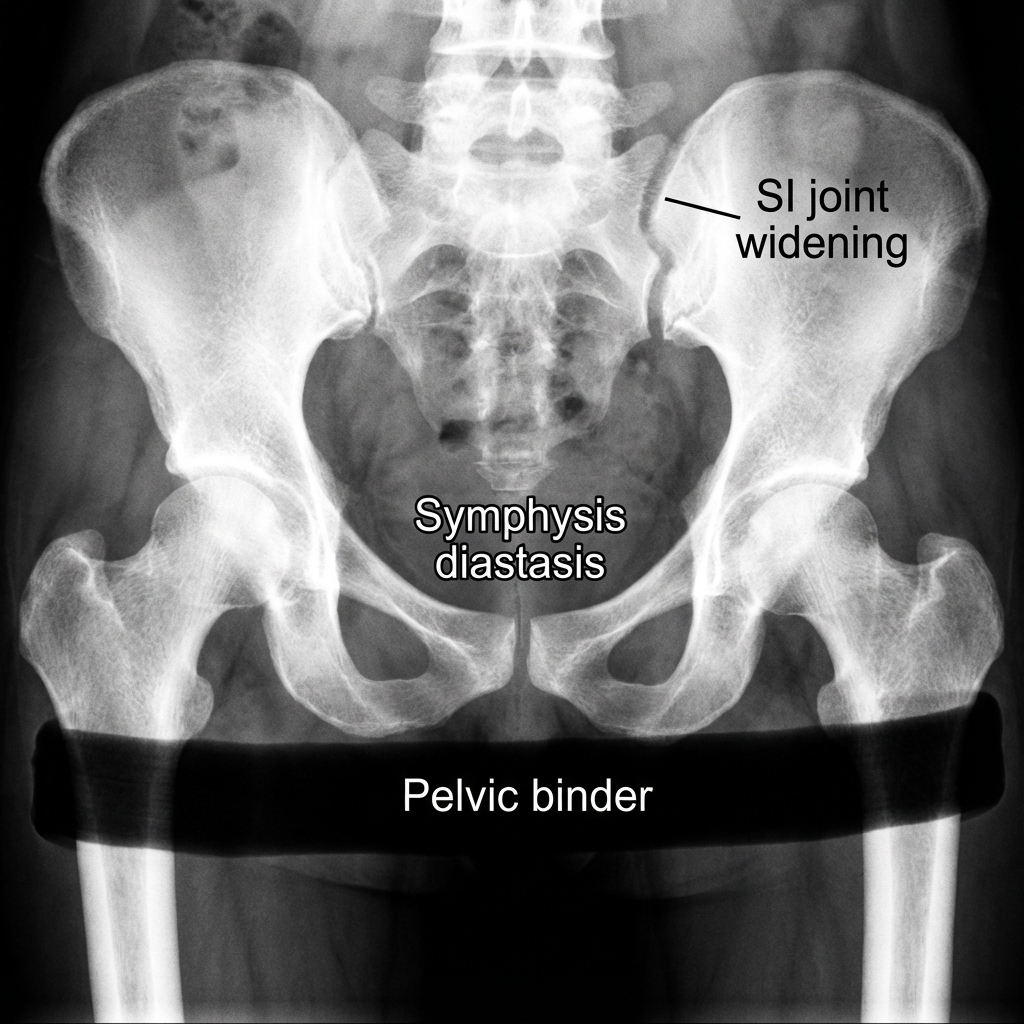

AP pelvis radiograph showing APC-III (open book) injury with symphysis pubis diastasis >2.5cm and widening of the left sacroiliac joint. The hemipelvis is externally rotated indicating complete posterior ring disruption. Pelvic binder in situ.

Source: Educational radiograph of an APC-III pelvic ring injury β’ OrthoVellum Medical Education Team β’ OrthoVellum Educational Use